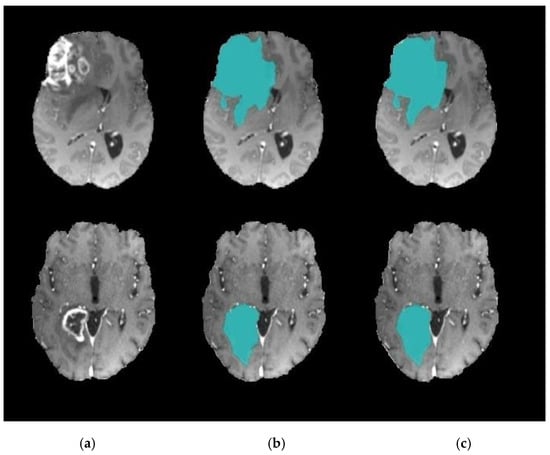

3.3. Level Set Segmentation

| 1: Insert initial contour points using two-step DA clustering output (ROI indexes). 2: Construct a signed distance function. 3: Calculate feature image using Gaussian filter and gradient. 4: Obtain the curve’s narrow band. 5: Obtain curvature and use gradient descent to minimize energy. 6: Evolve the curve. 7: Repeat step number two and stop after obtaining the segmented region. |